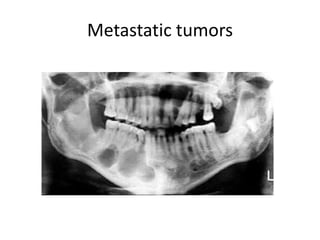

Metastatic tumors